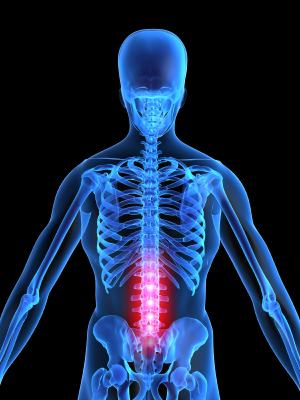

What is the ideal spinal alignment?

Notice that from the front, the spine is straight. From the side, however, the spine has three essential curves: a neck curve, a ribcage curve and a lower back curve.

The normal curves in the spine as seen from the side are extremely important for your health. These curves help absorb shock, allow for proper movement, and evenly distribute the normal forces on the spine.

If a spine deviates from the normal configuration, such as a significant increase, decrease or reversal of any of the curves, the spine is considered to be misaligned.

What causes misalignments of the spine?

Abnormal curves can be caused by injury, such as accidents or falls, or by poor postural habits.

What is the significance of spinal misalignments?

Spinal misalignments may cause increased stress on the muscles, ligaments, bones, discs, and nerves of the spinal column and surrounding tissues. These abnormal stresses can lead to a breakdown of body tissues that may result in pain, arthritis and other related symptoms.